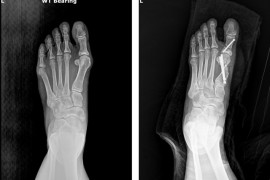

엄지발가락 휘고 통증 방치하면 못 걸을 수도폭 좁은 신발 신는 여성에 흔히 발병…초기엔 변형 적어 가볍게 넘기기도증상 심하면 뼈 위치·각도 교정 필요…'MICA 수술'로 최소 절개·빠른 회복걸그룹 '원더걸스'의 멤버이자 '24시간이 모자라', '가시나' 등의 히트곡을 낸 가수 '선미'는 원더걸스 활동 중이었던 2010년 돌연 활동을 중단한 적이 있다. 당시에는 학업을 이유로 활동을 중단한다고 밝혔지만, 실제로는 걸을 수 없을 정도로 악화된 무지외반증 때문이었다. 당시 '텔미', '쏘 핫', '노바디' 등으로 인기를 끌던 원더걸스의 스케줄은 쉴 틈이 없었고, 데뷔 전부터 앓고 있던 무지외반증은 치료시기를 놓쳐 끝내는 원더걸스 활동 중단에까지 이르게 만들었다.◆ 자연적으로 낫지 않는 질병선미의 가수활동을 중단시킬 정도로 심각한 질병인 무지외반증(Hallux Valgus)은 쉽게 말하면 '엄지발가락이 휘어지는 병'이다. 엄지발가락이 점점 바깥쪽으로 휘어져 첫 번째 중족골과의 각도가 넓어지면서, 발 안쪽이 돌출되는 대표적인 발 질환으로, 하이힐이나 폭이 좁은 신발을 자주 신는 여성에게 흔하다. 이 밖에도 선천적 요인, 평발, 관절 이완성 등도 발병에 영향을 미친다.초기에는 눈에 띄는 변형이 적어 '신발에 눌리는 통증' 정도로 가볍게 여기기 쉽다. 그렇게방치하다가 시간이 지나면 관절의 변형이 점점 심해지고 통증과 보행 불편해진다. 끝내는 두 번째 발가락이 빠지거나(탈구) 발이나 발가락에 관절염으로 이어질 수 있다.무지외반증이 무서운 이유는 자연적으로 원래 형태로 돌아가는 경우가 거의 없다는 점에 있다. 나호동 MS재건병원 족부·족관절클리닉 과장은 "초기에는 기능성 신발, 발가락 교정기, 패드 등의 보존적 치료를 시도할 수 있지만 돌아가는 각도가 커지고 관절염이나 발바닥 통증이 동반되면 비수술적 치료만으로는 일상생활의 불편을 해결하기 어렵다"고 말했다.특히 변형이 심해진 상태에서는 뼈의 위치와 각도를 교정해 주어야 하며, 이를 위해 결국에는 수술을 선택할 수밖에 없다는 게 전문의들의 의견이다.◆최근 수술 경향은 '작은 절개, 정밀 교정'무지외반증을 예방하는 방법 중 하나가 신발을 잘 고르는 것이다. 신발 때문에 발 변형이 올 가능성이 높다 보니 하이힐처럼 발볼이 좁고 굽이 높은 신발은 피하고 부드러운 재질에 앞 볼이 넓고 조이지 않는 신발을 고르는 게 중요하다. 또 발가락을 오므렸다 펴주는 스트레칭이나 마사지볼이나 공을 이용한 발바닥 마사지도 도움이 된다.무거운 체중도 발 모양의 변형을 부르기 때문에 적정 체중을 유지하는 것도 무지외반증 발생을 줄인다.무지외반증의 치료를 결정할 때는 변형의 정도, 통증의 강도, 일상생활에 미치는 영향, 환자의 기대치 등을 종합적으로 고려해야 한다.무지외반증의 치료법은 지속적인 연구와 학술 활동을 통해 발전해 왔는데, 최근 무지외반증에 적용되는 수술 방법으로는 절개 범위를 줄이고 회복을 빠르게 하는 최소침습 수술(MICA: Minimally Invasive Chevron-Akin Osteotomy)이 점차 널리 시행되고 있다.약 1㎝ 미만의 작은 절개로 특수 기구를 넣어 뼈를 자르고 교정한 뒤, 실시간 투시 영상(C-arm)으로 교정 상태를 확인하며 나사로 고정한다. 보고된 장점으로는 출혈과 부종이 적고, 흉터가 거의 남지 않으며, 비교적 빠른 시기에 체중 부하와 일상생활 복귀가 가능하다는 점 등이다.최소침습 수술에 관해서는 국내외 학회로부터 임상 결과, 수술 기구의 발전, 재발 방지 전략 등에 관한 연구가 꾸준히 발표되고 있다. 여기에 더해 여러 장기 추적 연구에서 만족도 높은 교정 결과와 기능적 회복이 확인되고 있다는 게 전문의들의 시각이다.나 과장은 "다만 일부 연구에서는 무리한 교정으로 인한 관절 강직, 과교정, 재발 등의 합병증도 있다는 지적이 있어 수술 적응증과 수술 술기의 표준화에 관한 논의가 활발히 진행되고 있다"고 밝히기도 했다.최소침습 수술은 작은 절개와 빠른 회복이 장점이지만, 뼈 교정과 고정 과정에서 고도의 기술과 경험이 요구된다.나 과장은 "최소침습 수술은 단순히 '작게 절개한다'는 개념에 그치지 않으며, 변형의 회전, 전위, 단축을 3차원적으로 교정해야 하므로 해부학적 이해와 충분한 경험이 필요한 고난이도 수술로 분류된다"며 "수술이 필요하다고 판단될 경우에는 무지외반증과 족부 최소침습 수술에 대한 충분한 임상 경험과 연구적 근거를 갖춘 의료진과 상담을 통해 치료 계획을 세우는 것이 바람직하다"고 조언했다.도움말 나호동 MS재건병원 족부·족관절클리닉 과장이화섭 기자 lhsskf@imaeil.comhttps://www.imaeil.com/page/view/2025082610130724321